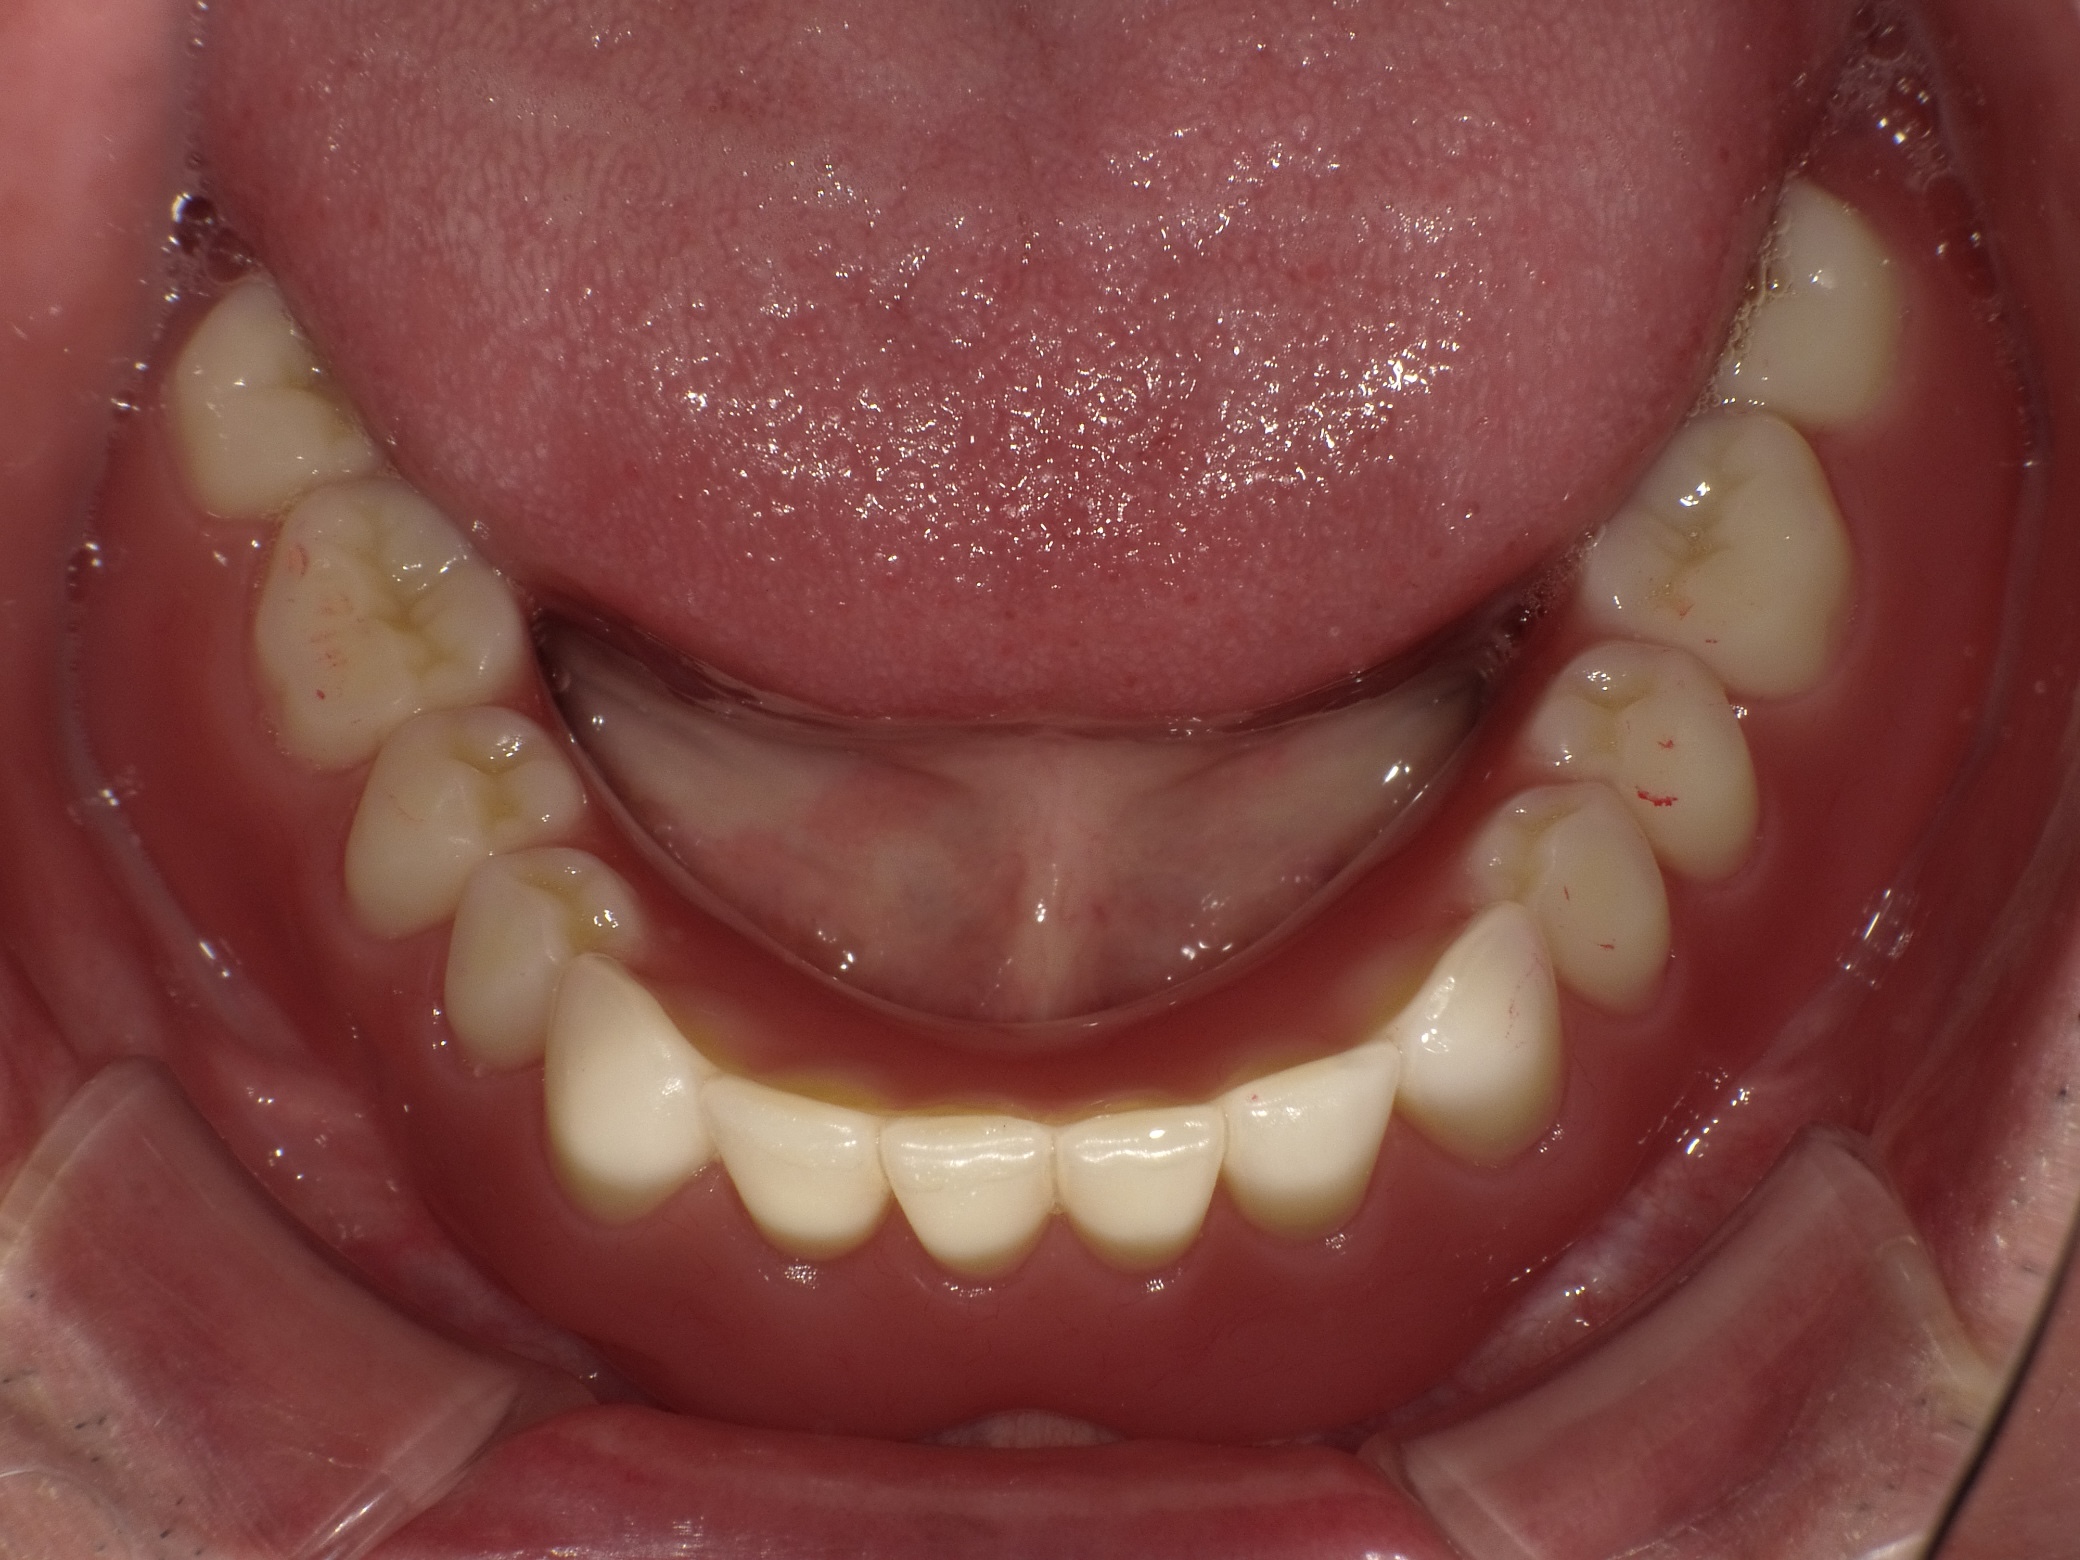

インプラントオーバーデンチャー症例

主訴 しっかり噛んで美味しいものを食べたい(男性) 治療内容 保存不可能な歯を抜歯後、2本のインプラントを埋入。

インプラントのアタッチメントと入れ歯の留め具とで凹凸接続し、動かない快適な入れ歯を装着しています。治療期間 約4ヶ月 費用 総額 ¥880,000–(税込) リスクと副作用 ・外科治療となるので、お身体の状態によっては受けれない場合がある(広範囲に適用可能な治療ですが、個々の患者様の状況によって適用外な場合もある)

・術後に多少の痛みや腫れが出ることがある